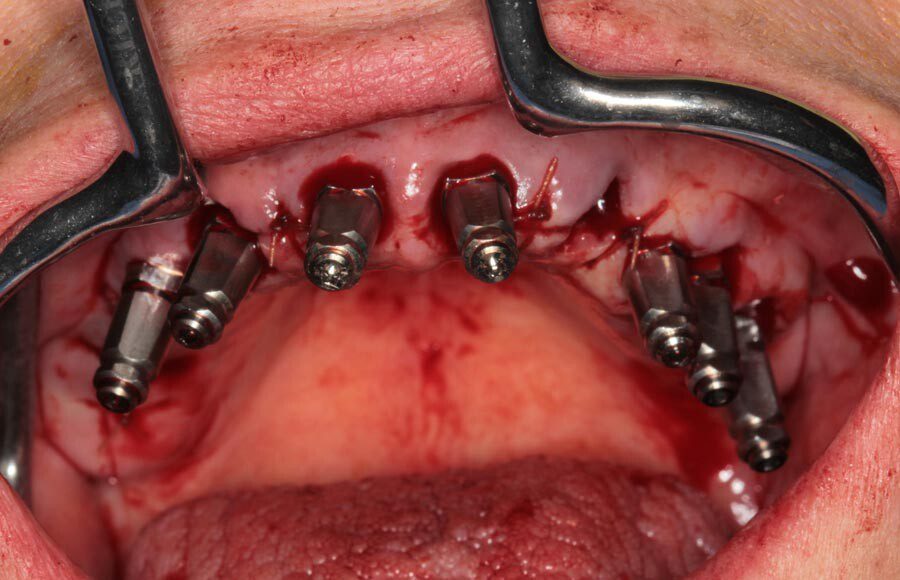

Teeth were removed and dental implants were placed. Because the bone was dense and the implants could be inserted with good primary stability, we were able to make impressions and load the implants that day.

Teeth were removed and dental implants were placed. Because the bone was dense and the implants could be inserted with good primary stability, we were able to make impressions and load the implants that day.